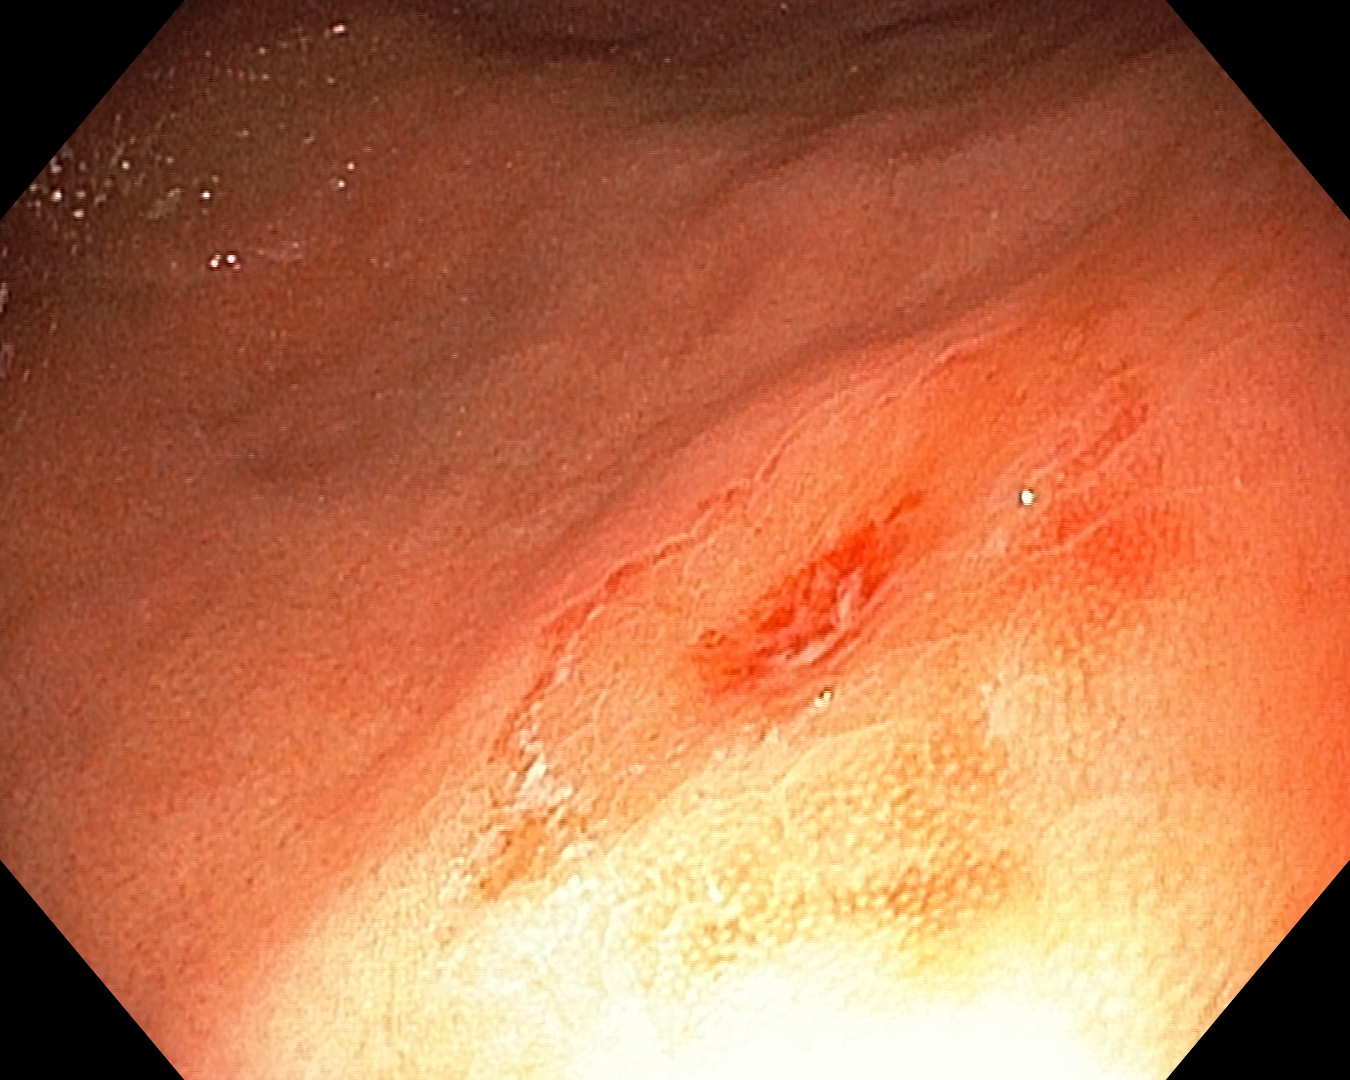

Дитині провели ургентне комбіноване втручання. Спочатку під час ендоскопії зі шлунка без розрізу вилучили 12 магнітів, при цьому вже були помітні ушкодження слизової оболонки. Оскільки ще п’ять магнітів залишалися в кишківнику, медики виконали операцію та за допомогою інтраопераційної колоноскопії обережно перемістили їх і вилучили природним шляхом.

У результаті лікарям вдалося дістати всі 17 магнітів. Найважливіше — у дитини не виявили перфорації кишківника, перитоніту чи некрозу, що дозволило уникнути тяжких ускладнень завдяки своєчасній медичній допомозі.